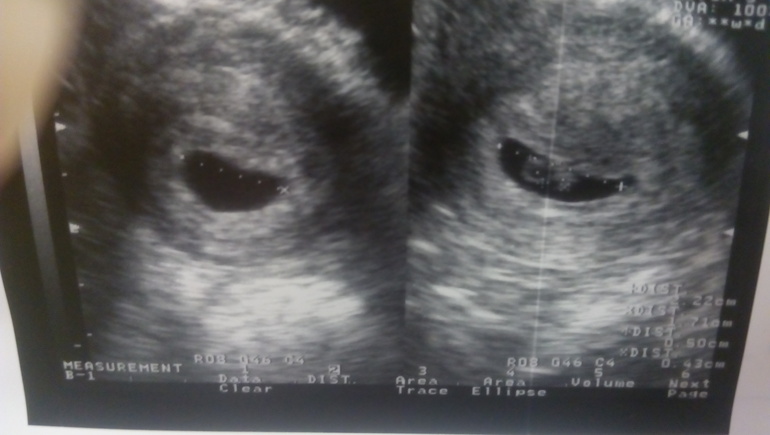

Результаты УЗИ

Я БЕРЕМЕННА !Всем привет! Напишу как мы сходили на наше первое УЗИ (про переживания писать не буду))) И так, на УЗИ мы пошли на 28 ДПП 3-дневочек и вот что нам написали в заключении:

ПЯ - 22*17 мм

ЖМ - 5 мм

КТР - 0,43 см

СБ +

Если честно, меня смущает, почему не померяли размер матки, и не сказали где прикрепилось ПЯ. А еще не сказали СВД ПЯ(((

И ещё вопросик, мне кажется, или ПЯ должно быть не такой формы?